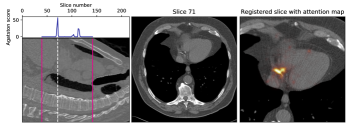

V-C Decision feedback

Decision feedback visualizes attention of the calcium scoring ConvNet. This feedback informs and end-user about the regions that contributed to the calcium score. Figure 7 shows examples of such feedback. The feedback helps an expert to quickly navigate and evaluate the image slices containing CAC.

We propose visual feedback as an optional qualitative tool, but we have performed a quantitative analysis to provide insight in its accuracy. To obtain quantitative results we analyzed heatmaps for slices with predicted calcium scores. The heatmaps were warped to the original image spaces by using the inverse transformation matrices. The values of the heatmaps were scaled between 0 and 1 to mimic probability maps for CAC candidate voxels. CAC candidates were defined as high density 26-connected voxels with a volume between 1.5 and 1,500 mm3[19]. For evaluation of these maps we performed precision-recall analysis (Figure 8). We have defined an optimal threshold by selecting the maximum F1 (i.e. Dice) score on the validation set. Table IV shows the obtained scores using the selected threshold on the test sets. The results show that detection performance is very accurate on the validation set as well as the test set.

Additionally, decision feedback aided our analysis by clarifying incorrect calcium scores. Decision feedback revealed that the largest CVD miscategorizations were not caused by incorrect quantification but by incorrect recognition of CAC. Figure 9 shows six examples of the largest miscategorizations made by the calcium scoring ConvNet. The majority of errors were made in identification of calcifications near the coronary artery ostia. Calcifications near the ostia can be partly in the aorta and partly in the coronary artery. These calcifications are difficult to distinguish, especially when no information of neighboring slices is available.